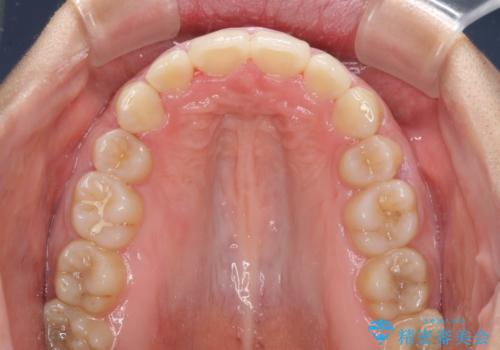

- 上下の出っ歯を気にして来院された患者様です。

口元を積極的に引っ込めるために、上下左右の第一小臼歯を4本抜歯することとしました。

しっかりと通院するようになってからは順調に治療が進み、横顔の印象が変わるほどスッキリとした口元となりました。